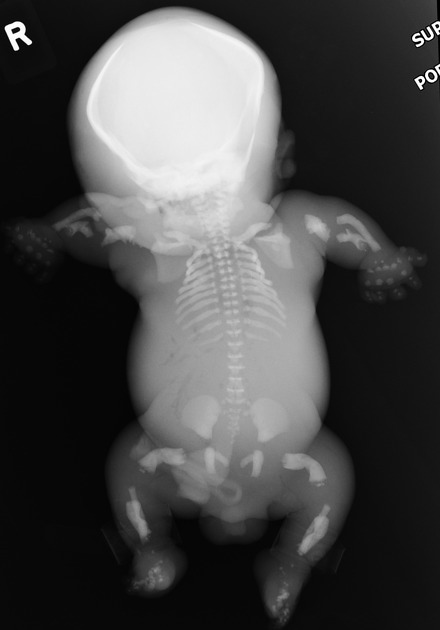

Tanatophoric dysplasia

A

Most common lethal skeletal dysplasia followed by osteogenesis imperfecta type II.

Mutation coding for the fibroblast growth receptor 3 (FGFR3)

type I:

marked underdevelopment of skeleton, telephone handle femurs more pronounced

type II

the presence of a cloverleaf skull may be a distinctive feature

limb shortening milder and bowing is not a feature

How well did you know this?